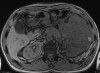

ФОТО дня

ОГРОМНАЯ опухоль левой почки с тромбом29.03.16